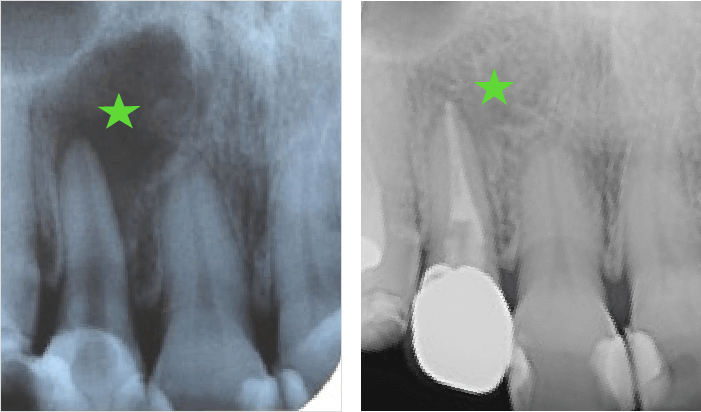

骨の再生が確認された症例(右上前歯)Case Study

レントゲン写真

顕微鏡下で感染源を徹底的に除去し、封鎖性を高めることで、半年後に骨の再生が確認されました。